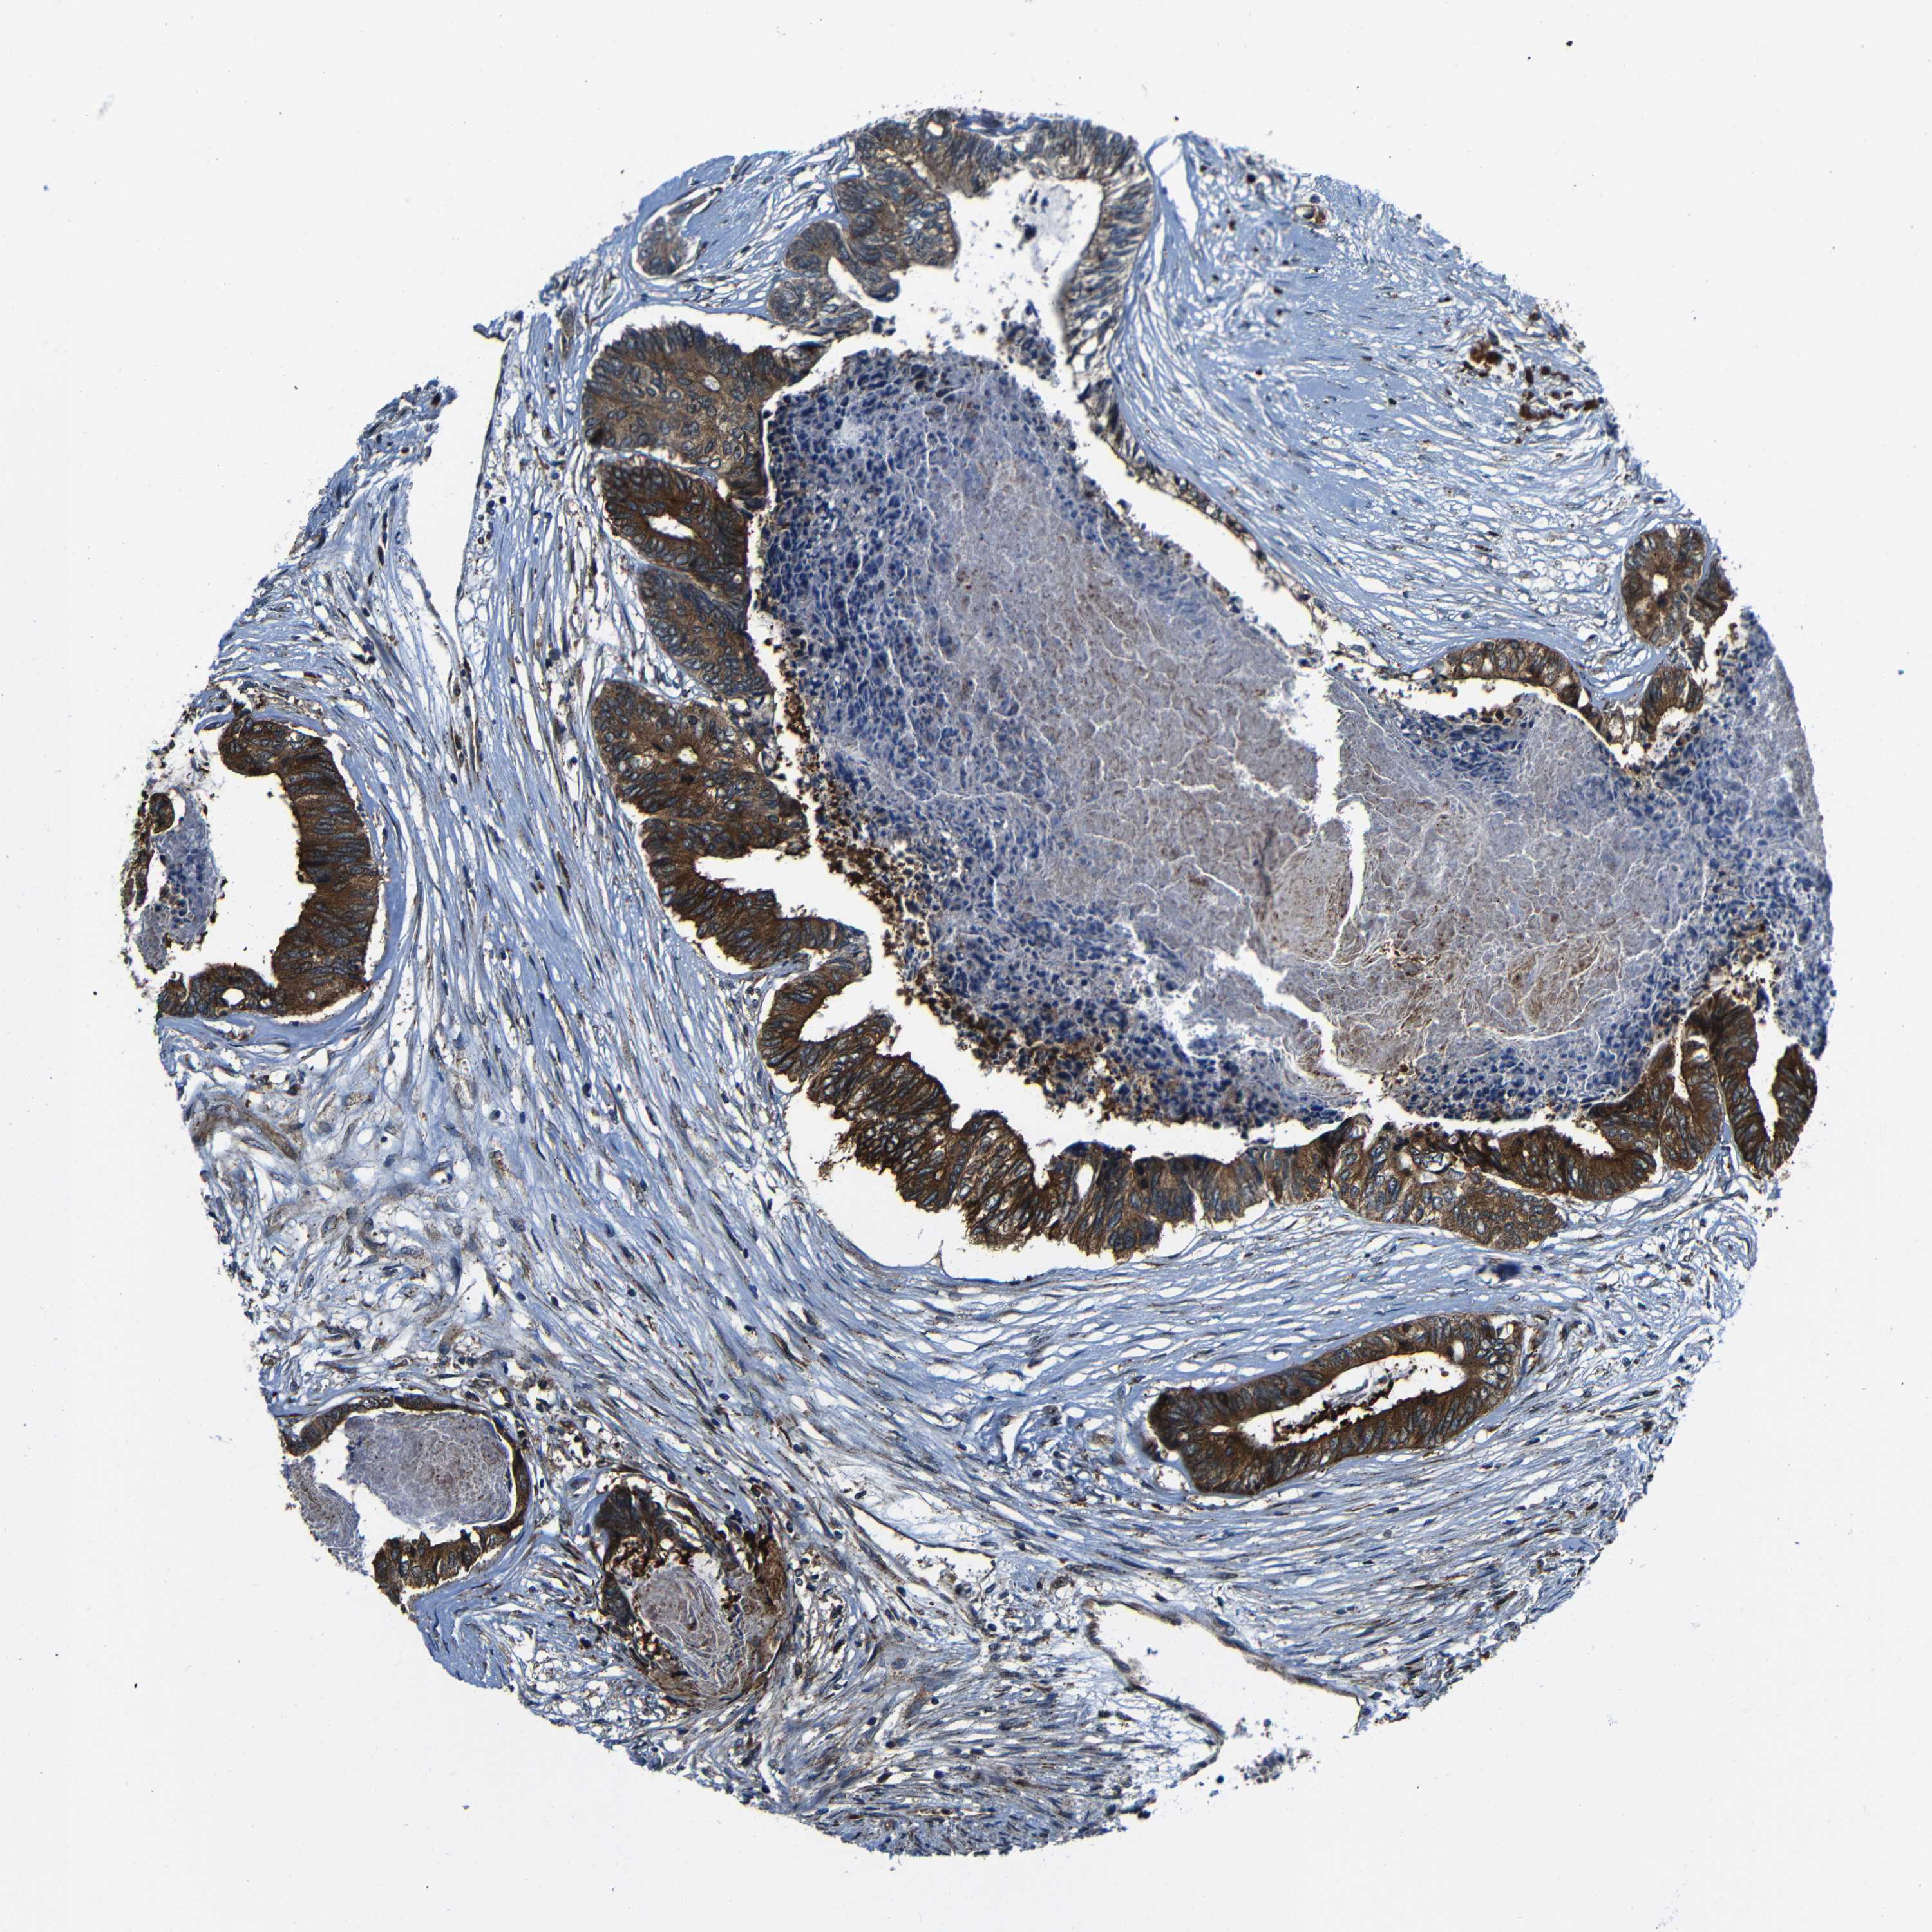

CANCER COLORECTAL CANCER Show tissue menu

Colorectal cancer

Human cancer

Colon adenocarcinoma